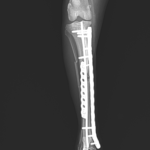

13歳のトイ・プードルがソファーからジャンプした際に後肢を傷めて救急病院を受診されました。エックス線検査で脛骨近位部の粉砕骨折(comminuted tibial fracture)が確定され、骨固定術の依頼がありました。小型犬では、ソファーやベッドなどの高さからのジャンプでも骨折が起こることがあります。特に高齢になると、骨密度の低下、骨皮質の菲薄化などにより、比較的弱い外力でも骨折が起きやすくなるため注意が必要です。今回の患者さんではOrthogonal ロッキングプレート固定+髄内釘(Plate–Rod construct)により骨折部を安定化しました。粉砕骨折では骨片を無理に整復せず、生物学的固定(biologic fixation)により自然な骨癒合を促す方法が現在の主流です。高齢犬でも適切な固定を行えば、良好な骨癒合と歩行回復が期待できます。